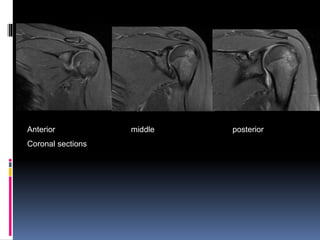

Anterior middle posterior

Coronal sections

Anterior middle

posterior